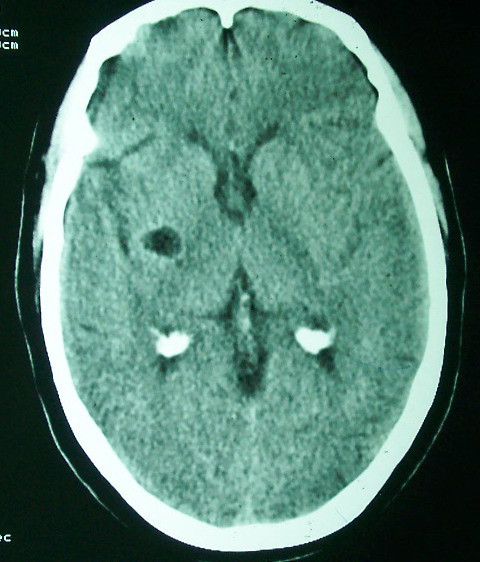

标题: CT18022:颅内多发稍高密度影

f     60    左侧肢体活动无力3天余,    神志情,  无抽搐史   无发热   否认囊虫接触史

有囊有节有钙化,这个表现符合混合型脑囊虫病.请结合临床资料并进行补体结合试验.

有囊有节有钙化,考虑混合型脑囊虫病.